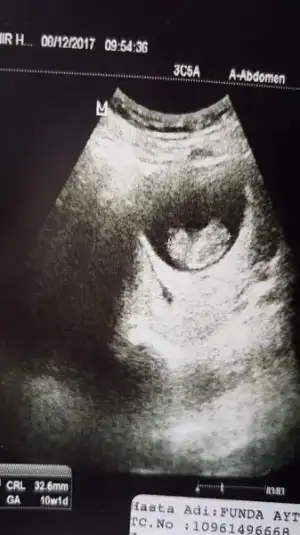

Yaa kızlar merhaba,

Benimkine de bakar mısınız rica etsem çok kafam karıştı :D

2'si de karından ve farklı hastanelerden aldığım fotoğraflar, tam anlayamadım açıkçası

Eklentiler

• 20171204_152838.webp

20171204_152838.webp

12,2 KB · Görüntüleme: 113

• received_10156299699248287.webp

received_10156299699248287.webp

19,7 KB · Görüntüleme: 134